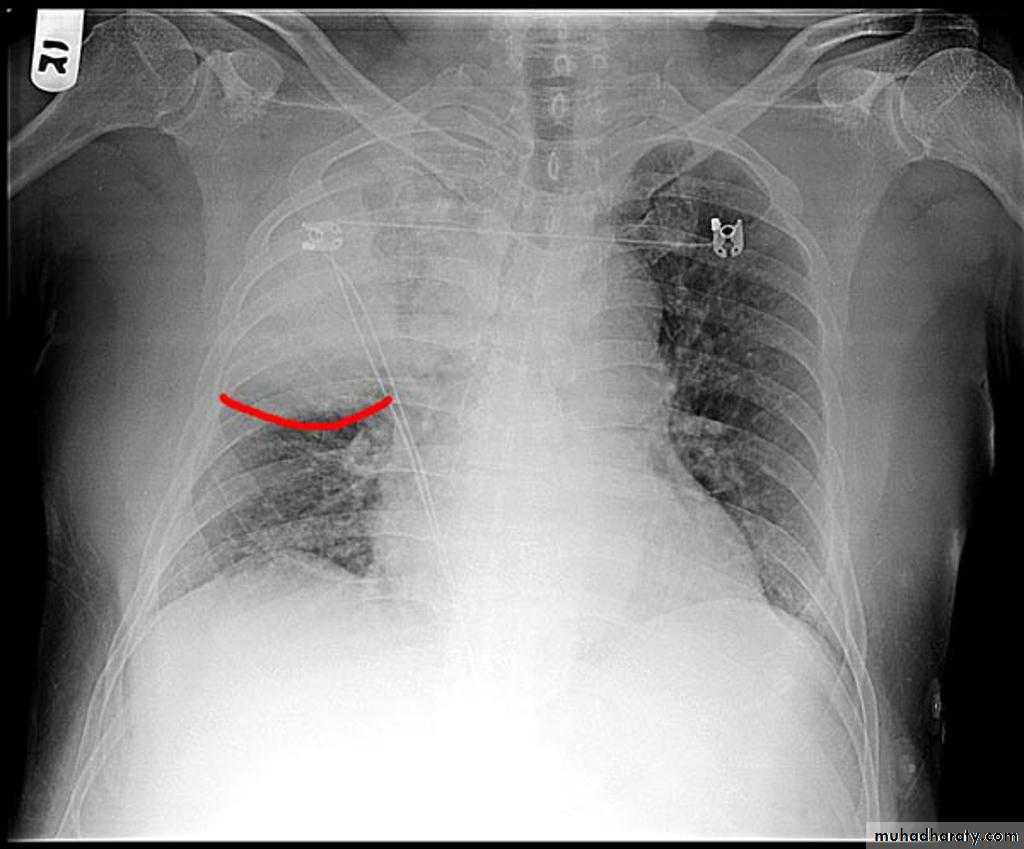

Pleural effusion

50.pleural effusion

51.pleural effusion .